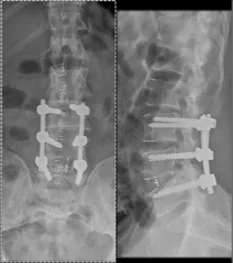

Before & After Clinical Gallery

We showcase real patient cases (with consent), including:

• Pre- and Post-operative MRIs and X-rays

• Disc Herniations, Stenosis, and Spondylolisthesis cases

• Visible improvement in alignment and decompression

Before

After